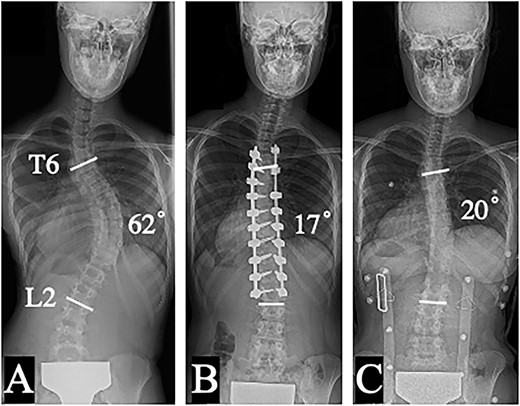

A 13-year-old girl was diagnosed with AIS classified as Lenke type 1A- since her standing radiographs demonstrated the main thoracic (MT) curve of 62° from T6 to L2, the thoracic kyphosis (TK) angle of 7° (Figs 1A and 2A). Posterior corrective surgery was performed at the T5-L2 level to prevent the progression of deformity. The MT curve was corrected to 17°, indicating a correction rate of 72.6%. The TK improved to 27° and acquired physiological kyphosis. At the 1-year follow-up, both the coronal and sagittal alignments were maintained, and the patient restarted sports activities without any impairment (Figs 1B and 2B). However, the patient returned to our hospital complaining of wound swelling 1 month later. Laboratory data showed a mild inflammatory reaction, but magnetic resonance imaging showed subcutaneous fluid accumulation, and its culture revealed Methicillin-susceptible Staphylococcus aureus. Although the infection subsided with debridement surgery and antibiotics, it recurred 3 months later. Inevitably, implant removal surgery was performed after confirming bony fusion by computed tomography (CT) scan. Following this, there was almost no loss of the coronal alignment; however, the sagittal alignment progressively deteriorated (Figs 1B, C). Even though hard bracing was introduced to prevent the progression of kyphotic change, the TK progressed to 74° in a year (Fig. 2C). As a result, the height of the patient decreased by 2.5 cm. The patient complained of back pain in the supine position and the radiograph revealed rigid thoracic hyper-kyphosis that was not corrected by fulcrum bending (Fig. 2D). Therefore, revision surgery was performed 15 months after implant removal. Solid bony fusion was confirmed from T5 to L2. However, slight intraspinal mobility was observed at T7/8 and T10/11, even though the preoperative CT scan showed no clear evidence of pseudarthrosis (Fig. 3A). Pedicle screws were placed from T2 to L3 using an O-arm navigation system due to the significant changes in anatomical structure. Schwab Grade 2 osteotomies were performed again with the removal of fusion masses at multiple levels including at T7/8 and T10/11and the kyphosis was corrected using the cantilever technique (Fig. 3B). At the 14 month follow-up, there was no evidence of recurrence or residual infection, and the MT and TK were corrected and maintained at 5° and 23°, respectively (Figs 4A, B).

Posteroanterior plain radiographs in a standing position: preoperative (A), and 1 year after posterior corrective surgery from T5 to L2 (B); 1 year after implant removal (C).